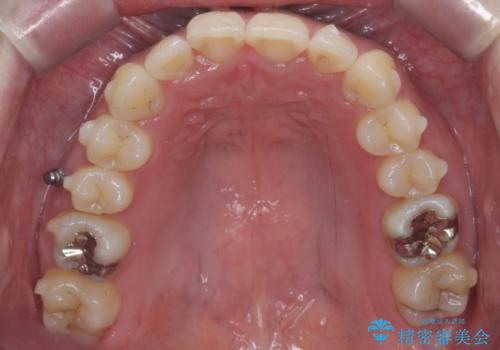

- 前歯のがたつきを主訴に来院。

前歯は目立つのでワイヤー矯正は絶対にしたくないとのことでした。

右上の奥歯を後ろに送り、前歯が出っ歯にならないように並べました。

また、右下の奥歯に一部目立たないように部分的なワイヤー矯正を行い、右下の奥歯が反対咬合になっていたのもしっかり中に入れて治療しています。